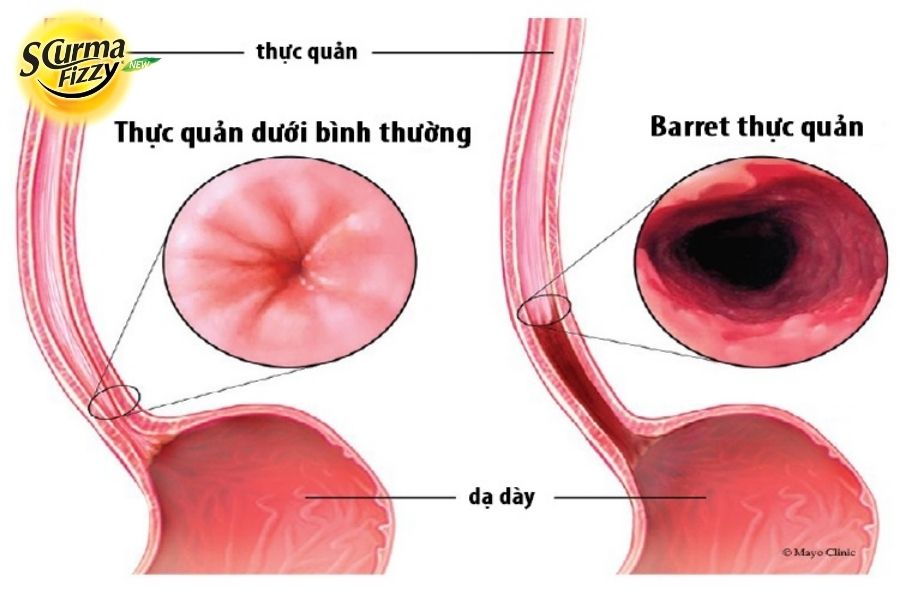

Barrett thực quản là sự thay đổi thành phần tế bào của màng nhầy thực quản. Thực quản bình thường được lót bằng một lớp tế bào dẹt (tế bào biểu mô vảy).

Trong thực quản của Barrett, những tế bào này được thay thế bằng một lớp tế bào dày hơn và cao hơn (tế bào biểu mô trụ) tương tự như những tế bào được tìm thấy trên bề mặt bên trong của dạ dày hoặc ruột. Việc thay thế một loại tế bào biệt hóa này bằng một loại tế bào biệt hóa trưởng thành khác được gọi là chuyển sản, và khác với sự biến đổi tế bào xảy ra trong quá trình tiến triển của ung thư.

Nguyên nhân chính của Barrett thực quản được cho là do thích ứng với việc tiếp xúc với acid mãn tính do viêm thực quản trào ngược. Barrett thực quản có thể làm tăng nguy cơ xuất hiện ung thư thực quản. Mặc dù nội soi thực quản có thể xác định những thay đổi mô tiềm ẩn là dấu hiệu của thực quản Barrett, nhưng để chẩn đoán xác nhận cần phải sinh thiết màng nhầy thực quản. Vì vậy, hãy áp dụng những cách chữa trào ngược dạ dày hiệu quả và an toàn nhất.

Bệnh Barrett thực quản là gì?